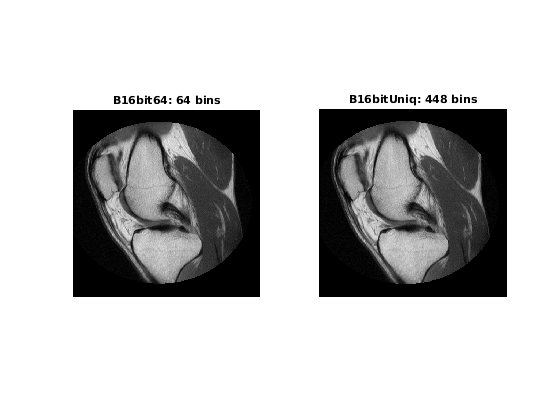

Важный поведенческий аспект этого алгоритма, чтобы отметить то, что как nbins увеличения значения, степени быстрых колебаний между смежным заполненным peaks в гистограмме изображения J имеет тенденцию увеличиваться. Это видно в следующих графиках гистограммы, взятых из 16-битного полутонового примера MRI.

Оптимальное значение для nbins представляет компромисс между большим количеством уровней на выходе (большие значения nbins) при минимизации пиковых колебаний гистограммы (меньшие значения nbins).